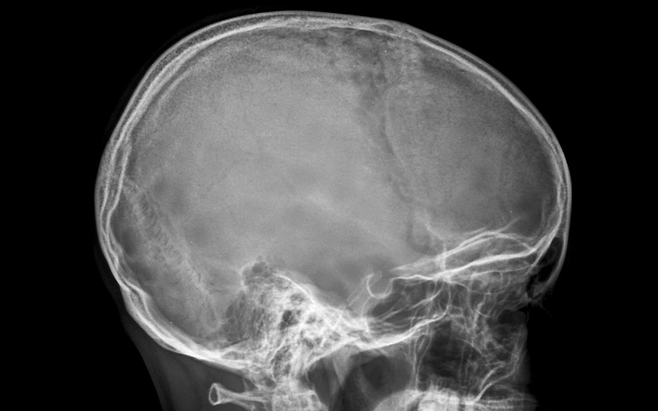

몸은 갑자기 망가지지 않습니다. 작은 이상 신호를 먼저 보냅니다.

특히 뇌혈관이 막히기 직전에는 일시적이고 애매한 증상이 나타나기도 합니다. “괜찮겠지” 하고 넘기기 쉬운 변화일수록 주의가 필요합니다.

뇌혈관 질환은 시간과의 싸움입니다. 증상이 사라졌다고 안심할 문제가 아닙니다.

한쪽 마비, 언어 이상, 갑작스러운 두통은 즉각적인 진료가 필요한 신호입니다. 몸이 보내는 경고를 무시하지 마세요. 빠른 대응이 뇌를 지킵니다.